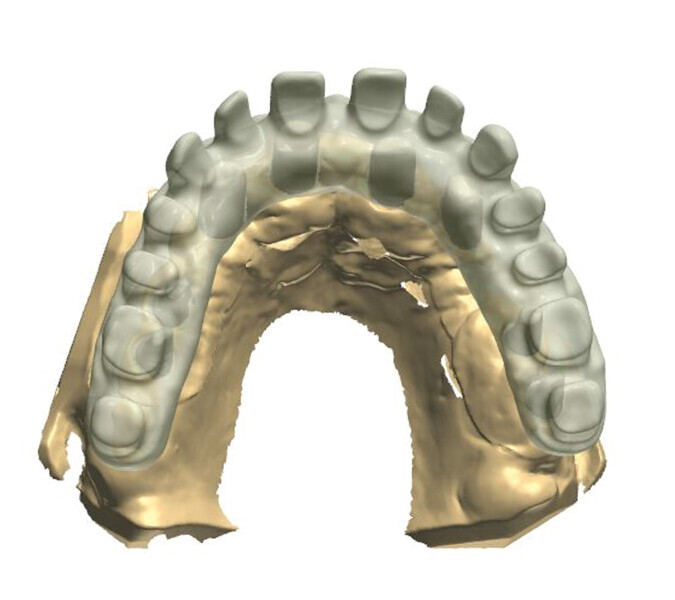

Fig. 1: A virtual image of a scanned model with abutments and telescopic crowns.